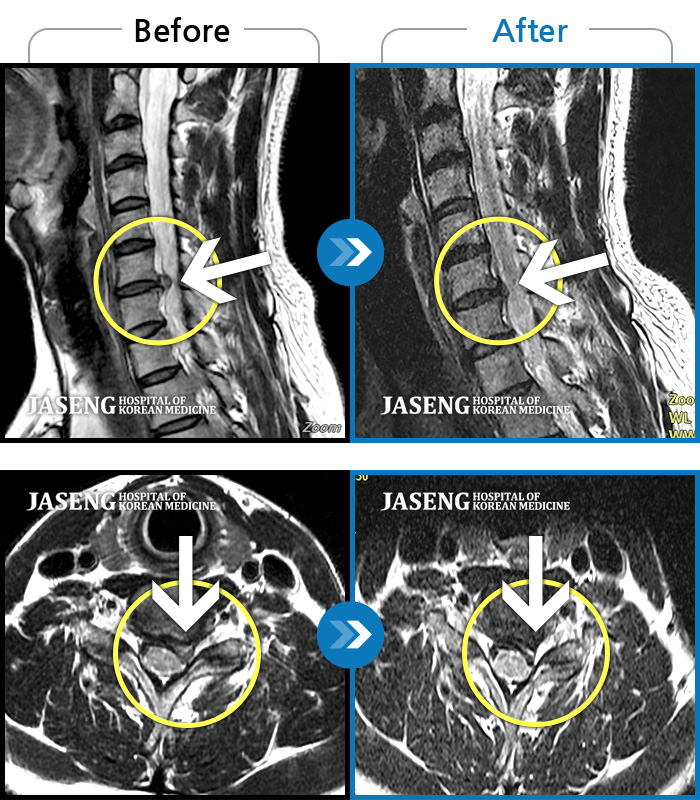

자생 비수술 한방통합치료 후

터진디스크가 흡수된 모습

비수술 치료만으로

터진 디스크 흡수

Before

After

목과 등이 찌르듯이 날카롭게 아프다.

2023.03.15 ~ 2025.05.31

좌측 목, 어깨, 상지 찌릿한 방사통으로 일상생활 지장, 야간통이 심하다

2023.06.09 ~ 2025.03.10